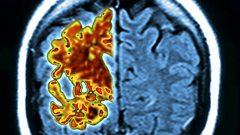

![]()  Early on-set dementia experiencesDuration: 00:53